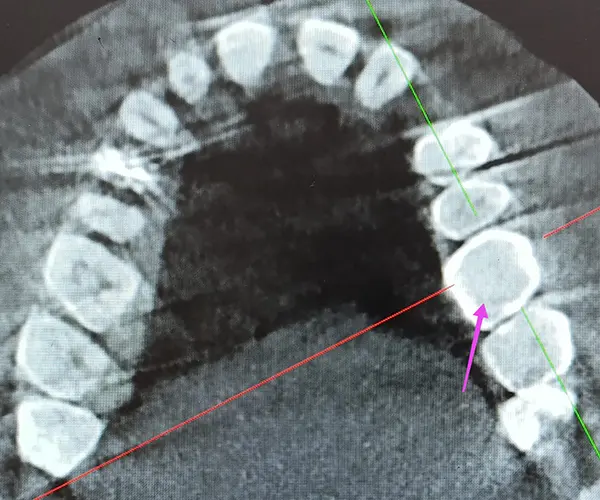

По результатам КЛКТ у пациента был выявлен дефект твердых тканей на дистальной поверхности зуба 2.6. Основной вызов — восстановить анатомию зуба, сохранив плотный апроксимальный контакт и обеспечив идеальную адаптацию композита к тканям зуба.

После этапа препарирования доктор принял решение работать в комбинированной технике с использованием материалов линейки B&E.